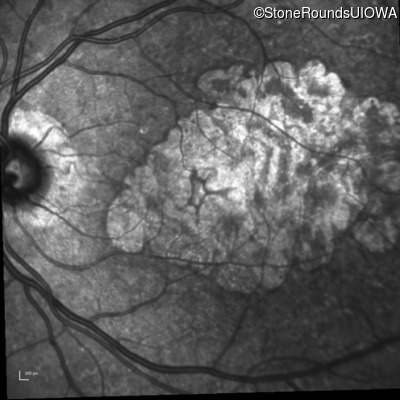

Blue Autofluorescence - Right - 20/40 -1

Exemplar

Blue Autofluorescence - Left - 20/63 -1